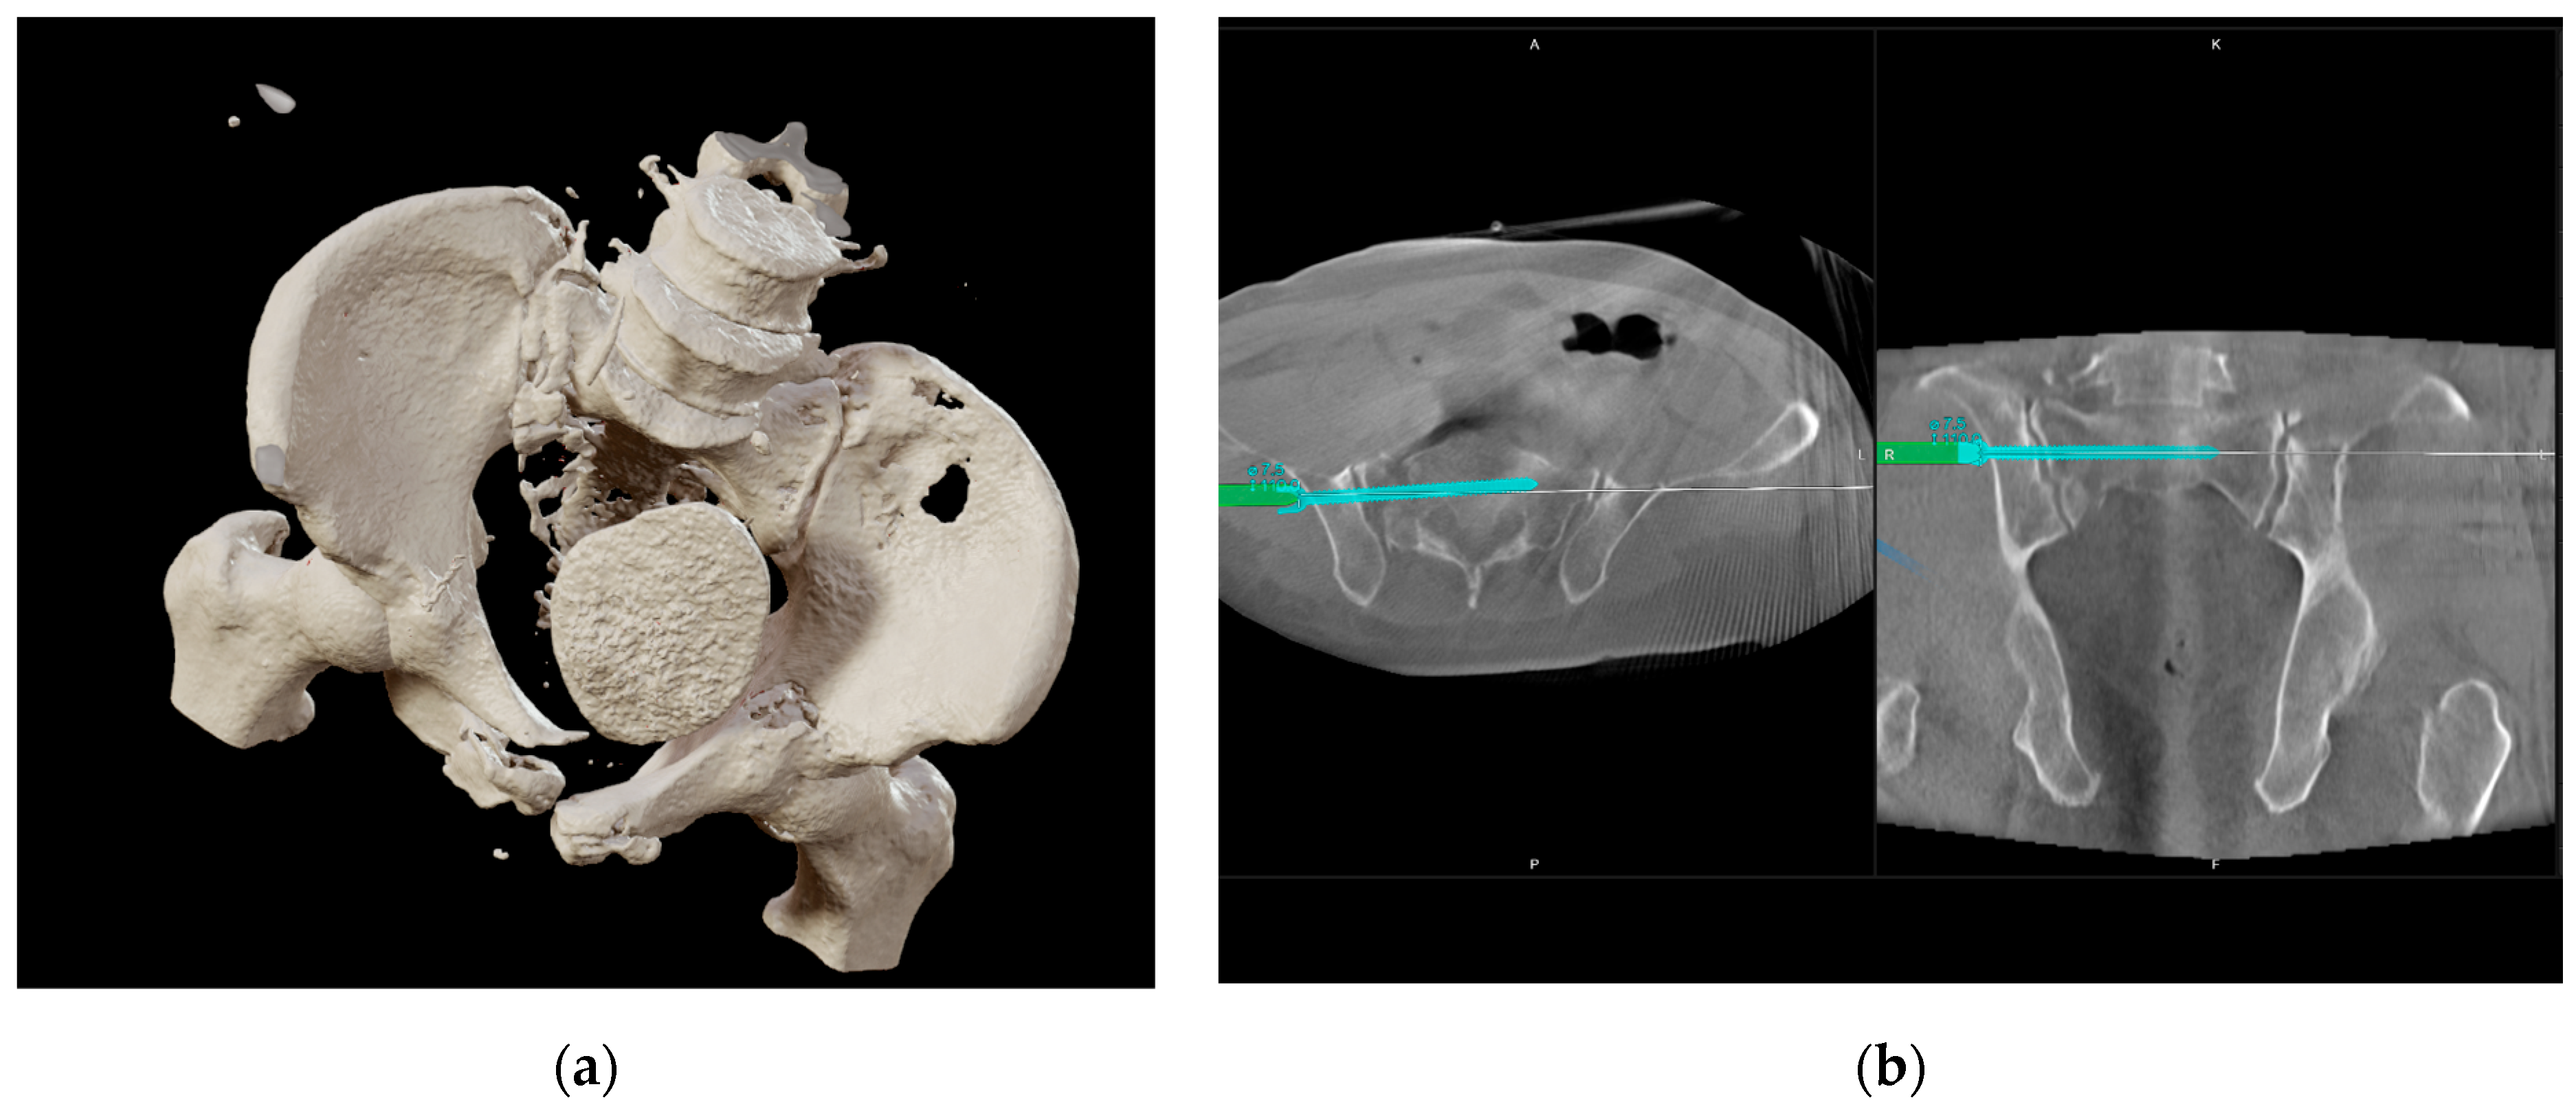

2.2. Injury Details and Initial Treatment

2.3. Indication